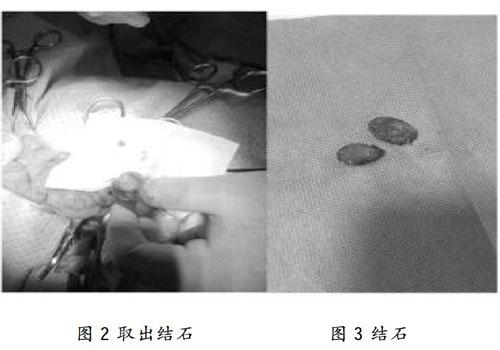

一例犬膀胱结石的治疗总结 参考网

一例犬膀胱结石的治疗总结 参考网

一例犬膀胱结石诊疗报告

一例犬膀胱结石的诊断与治疗